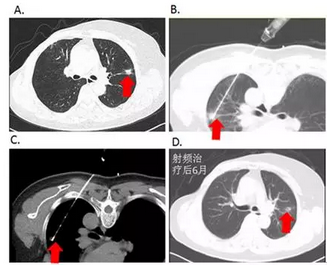

图1:CT引导下肺恶性肿瘤射频消融治疗

2.用于肺转移瘤的治疗。研究表明,肺转移瘤且直径≤2-3cm,接受RFA治疗的肺转移瘤患者,3年生存率为53.7%,4年生存率为44.1%。如图3所示,1例乳腺癌患者术后复发伴左肺单发转移,经RFA治疗后复查及随访近3年,生活质量良好,无远处复发。

图3:患者,女性,48岁,乳腺癌术后单发肺转移。